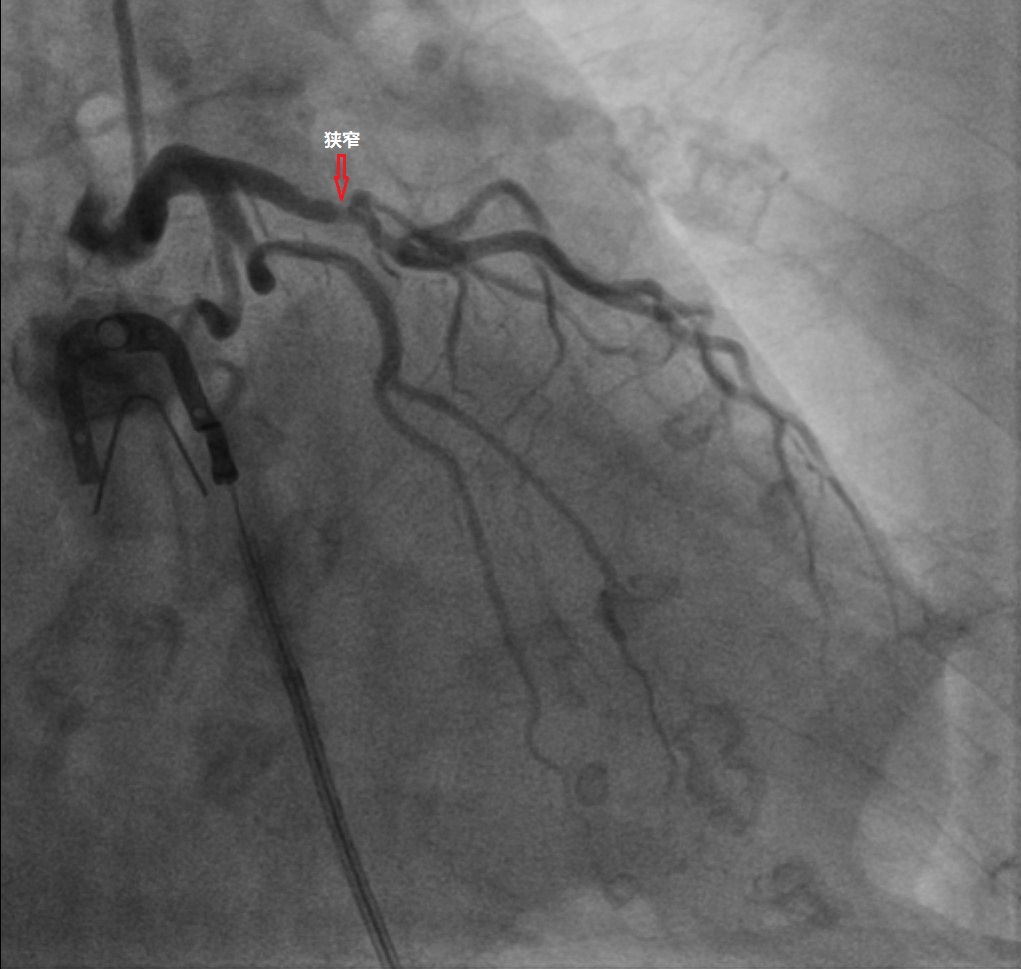

5. 冠状动脉造影(金标准)——“开灯查户口”

原理:导管从手腕/大腿插进去,直接把造影剂打进冠状动脉,实时拍片。

优点:最准确,能看到堵了多少、要不要放支架。

缺点:有创,需要住院,有少量风险(比如出血、造影剂肾病)。

适合:症状明显、CTA提示重度狭窄、准备做介入治疗的人。